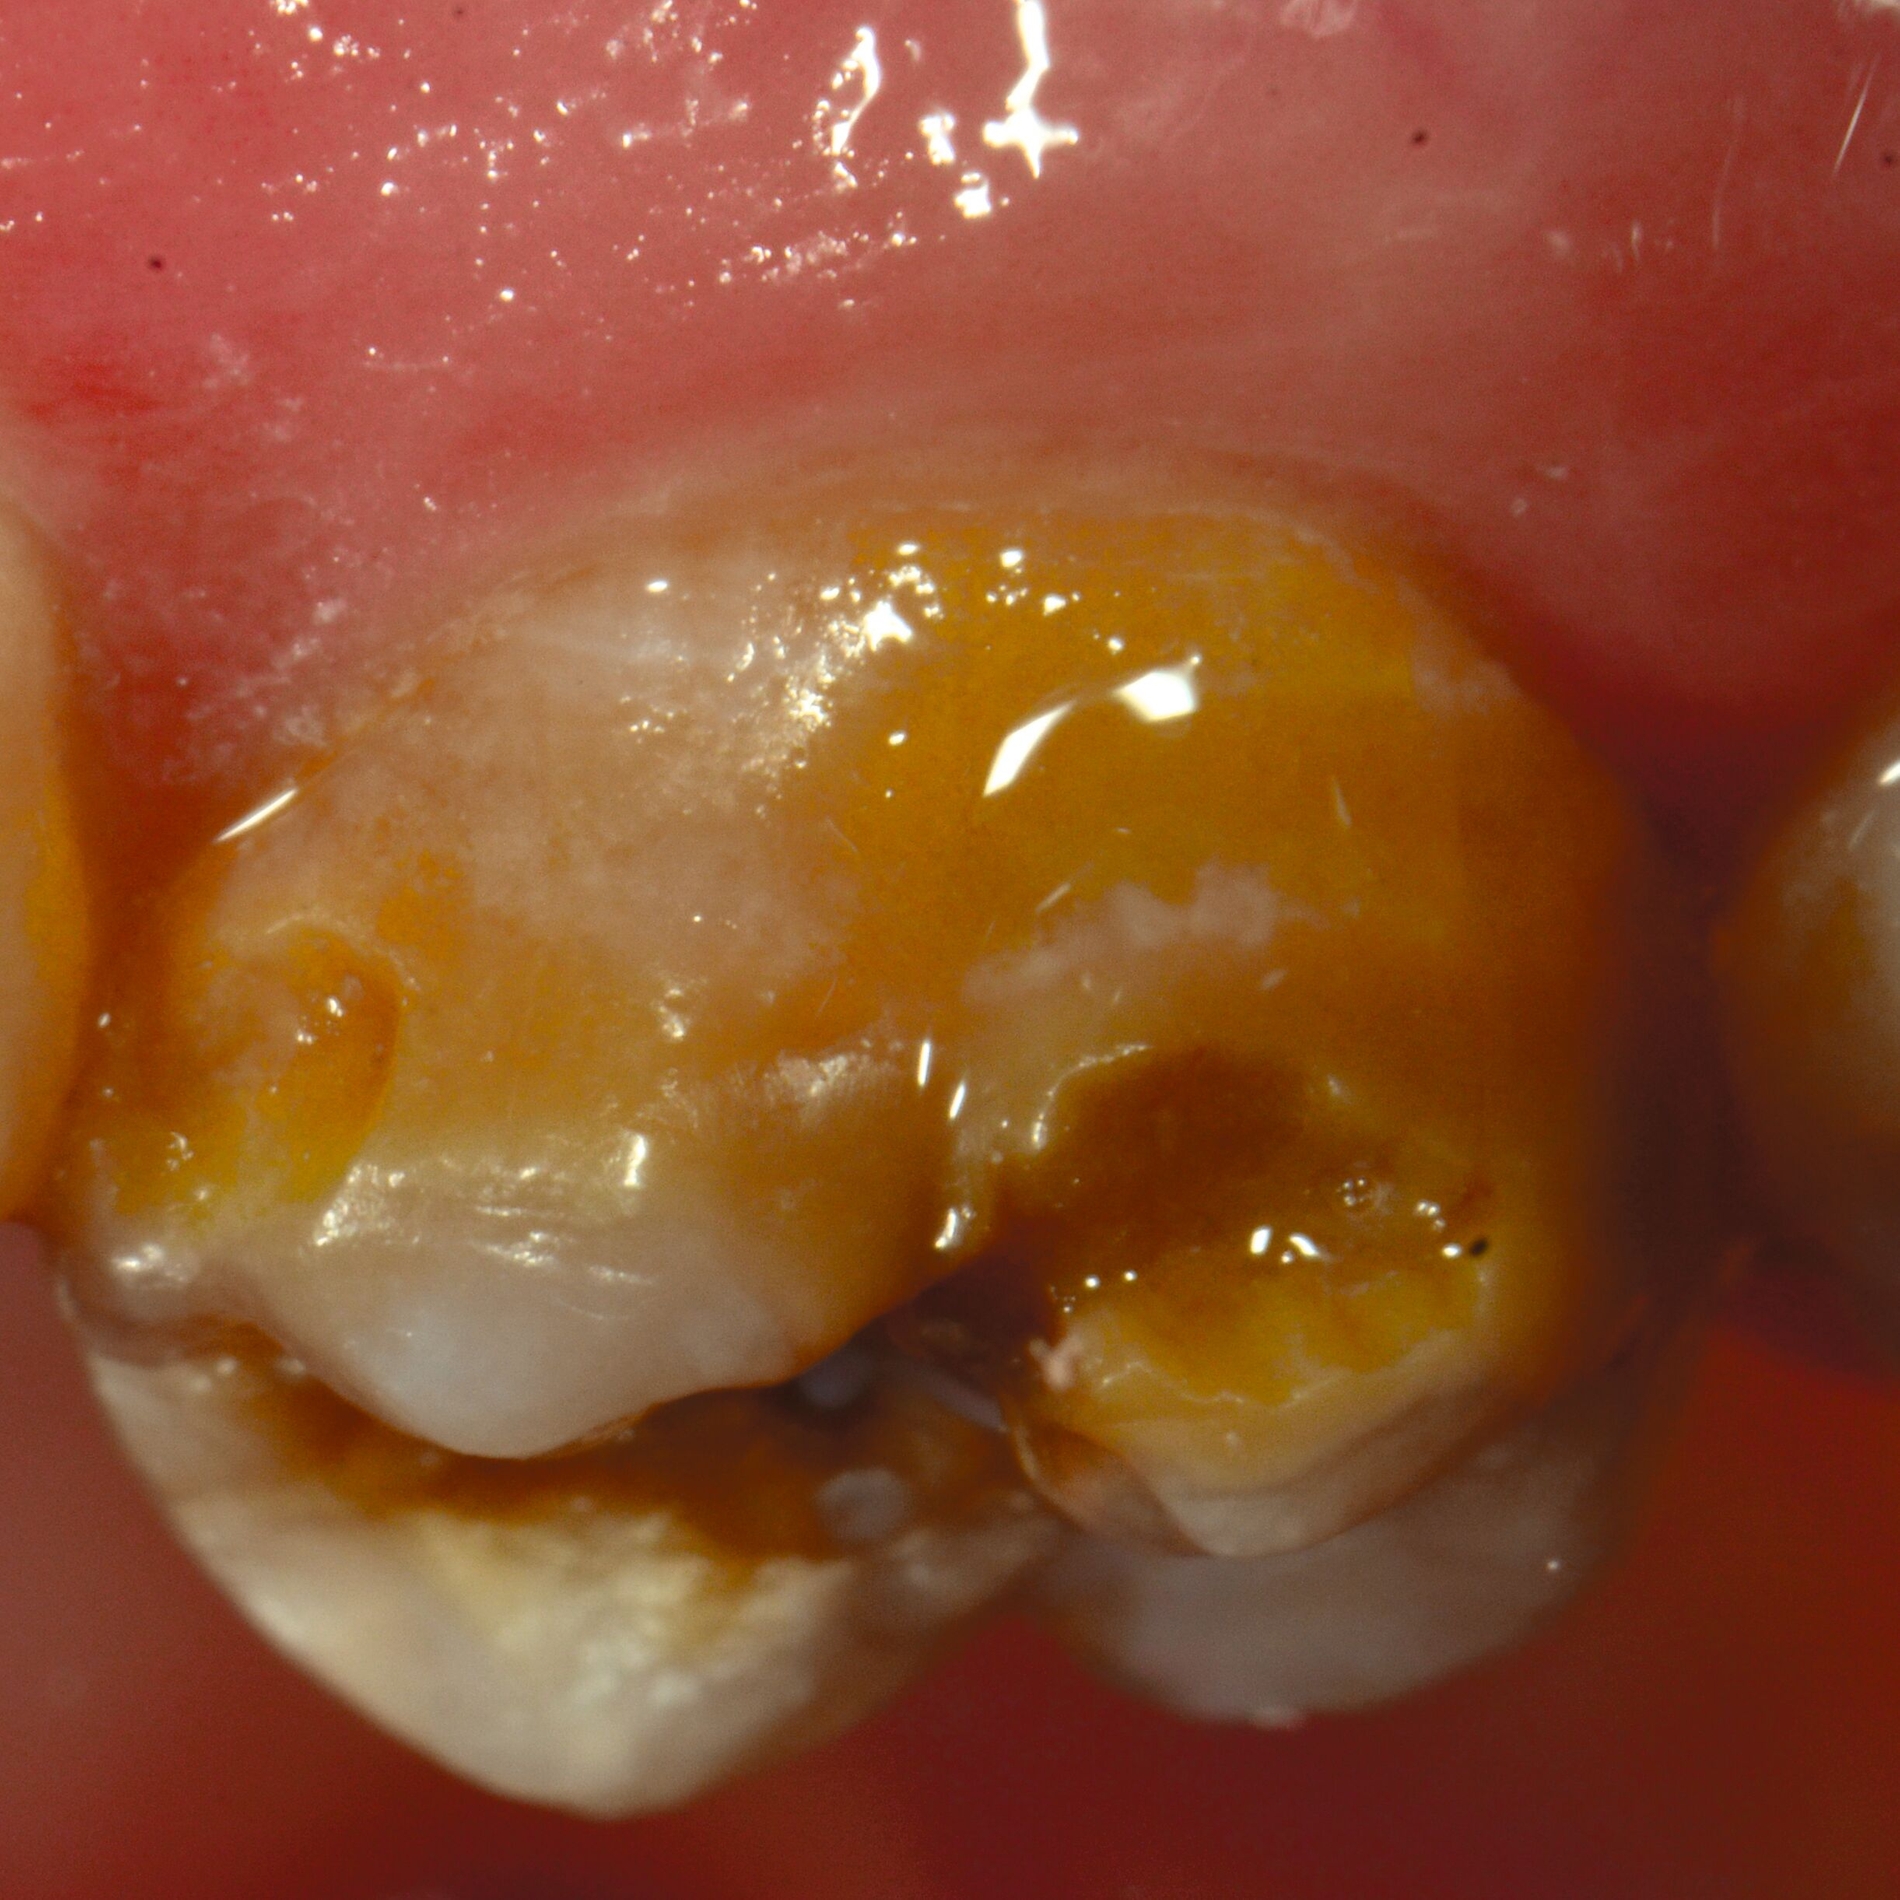

An umfangreich hypomineralisierten Zähnen können Schmelzeinbrüche (engl.: „enamel breakdown“ oder „enamel desintegration“, Abbildung 5) auftreten [Lygidakis et al., 2010; 2022]. Da diese oftmals die Folge einer fehlenden Belastungsfähigkeit des Zahnschmelzes sind und erst nach der Einstellung der Zähne in die Okklusion auftreten, werden sie auch als posteruptive Schmelzeinbrüche bezeichnet. Sie sind häufig im Bereich der Kauflächen beziehungsweise Höcker der Molaren zu finden, führen zur Dentinexposition und damit einhergehend zu ausgeprägten Hypersensitiven insbesondere bei Kindern, deren Zähne gerade erst durchgebrochen sind [Linner et al., 2021].

Frontzähne sind seltener von MIH-bedingten Schmelzeinbrüchen und Hypersensitivitäten betroffen. Von den posteruptiven Oberflächeneinbrüchen sind präeruptive Defekte abzugrenzen. Diese Zähne brechen bereits mit einem vorhandenen Oberflächendefekt in die Mundhöhle durch.

Für die Dokumentation und Klassifikation der MIH wurden verschiedene Systeme vorgeschlagen. Als historisch und veraltet gilt der (modifizierte) DDE-Index. Demgegenüber haben die Kriterien der EAPD – abgegrenzte Opazitäten (Abbildung 3 und 4), Schmelzeinbrüche (Abbildung 5), atypische Restaurationen (Abbildung 6) – mittlerweile die weiteste Verbreitung gefunden. Diese wurden 2003 erstmals zur Beschreibung der MIH auf empirischer Basis publiziert [Weerheijm et al., 2003] und den Jahren 2010 und 2022 im Rahmen der damaligen MIH-Workshops bestätigt [Lygidakis et al., 2010; 2022].